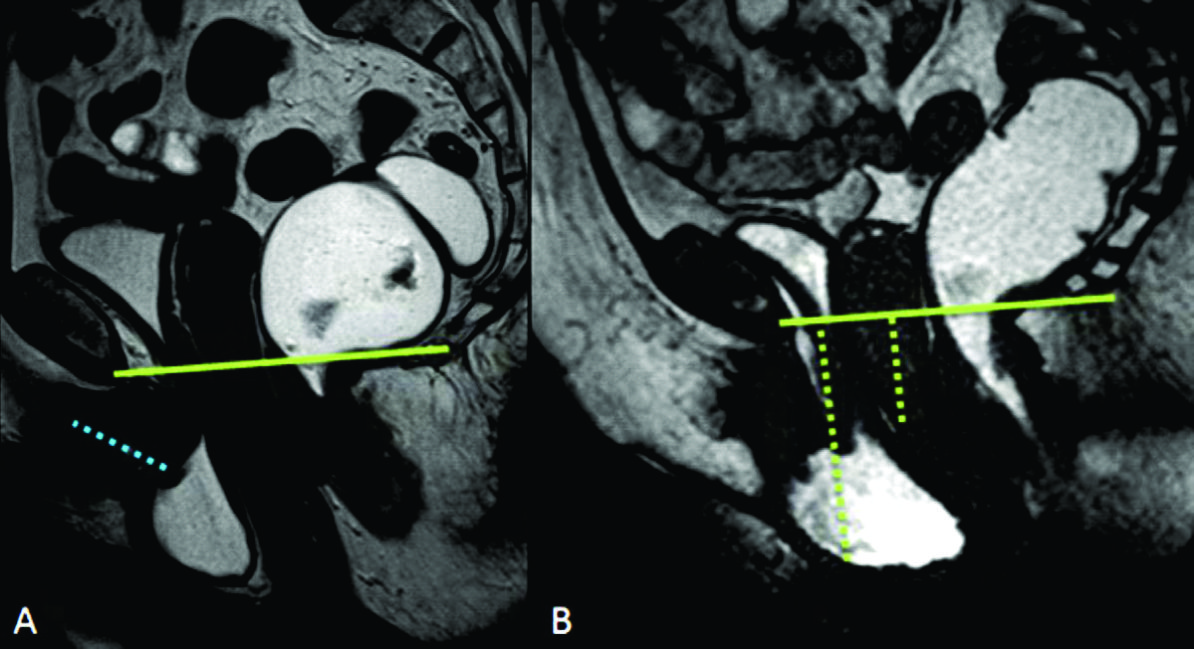

Figura 1

Evaluación anatómica. Líneas de referencia usadas para la valoración de la debilidad del piso pélvico. Imágenes potenciadas en T2 de alta resolución en el plano sagital a nivel de la línea media de una mujer durante el reposo. Recto distendido con gel ecográfico tibio. El útero no es bien visualizado dada su situación para mediana. A) PCL: Línea pubo-coccígea (línea continua). B) MLP: Línea media púbica (línea continua). Para evaluar el prolapso de los órganos pélvicos se trazan líneas perpendiculares desde los puntos de referencia anatómicos en los compartimentos anterior, medio y posterior hasta la línea PCL y/o MLP.